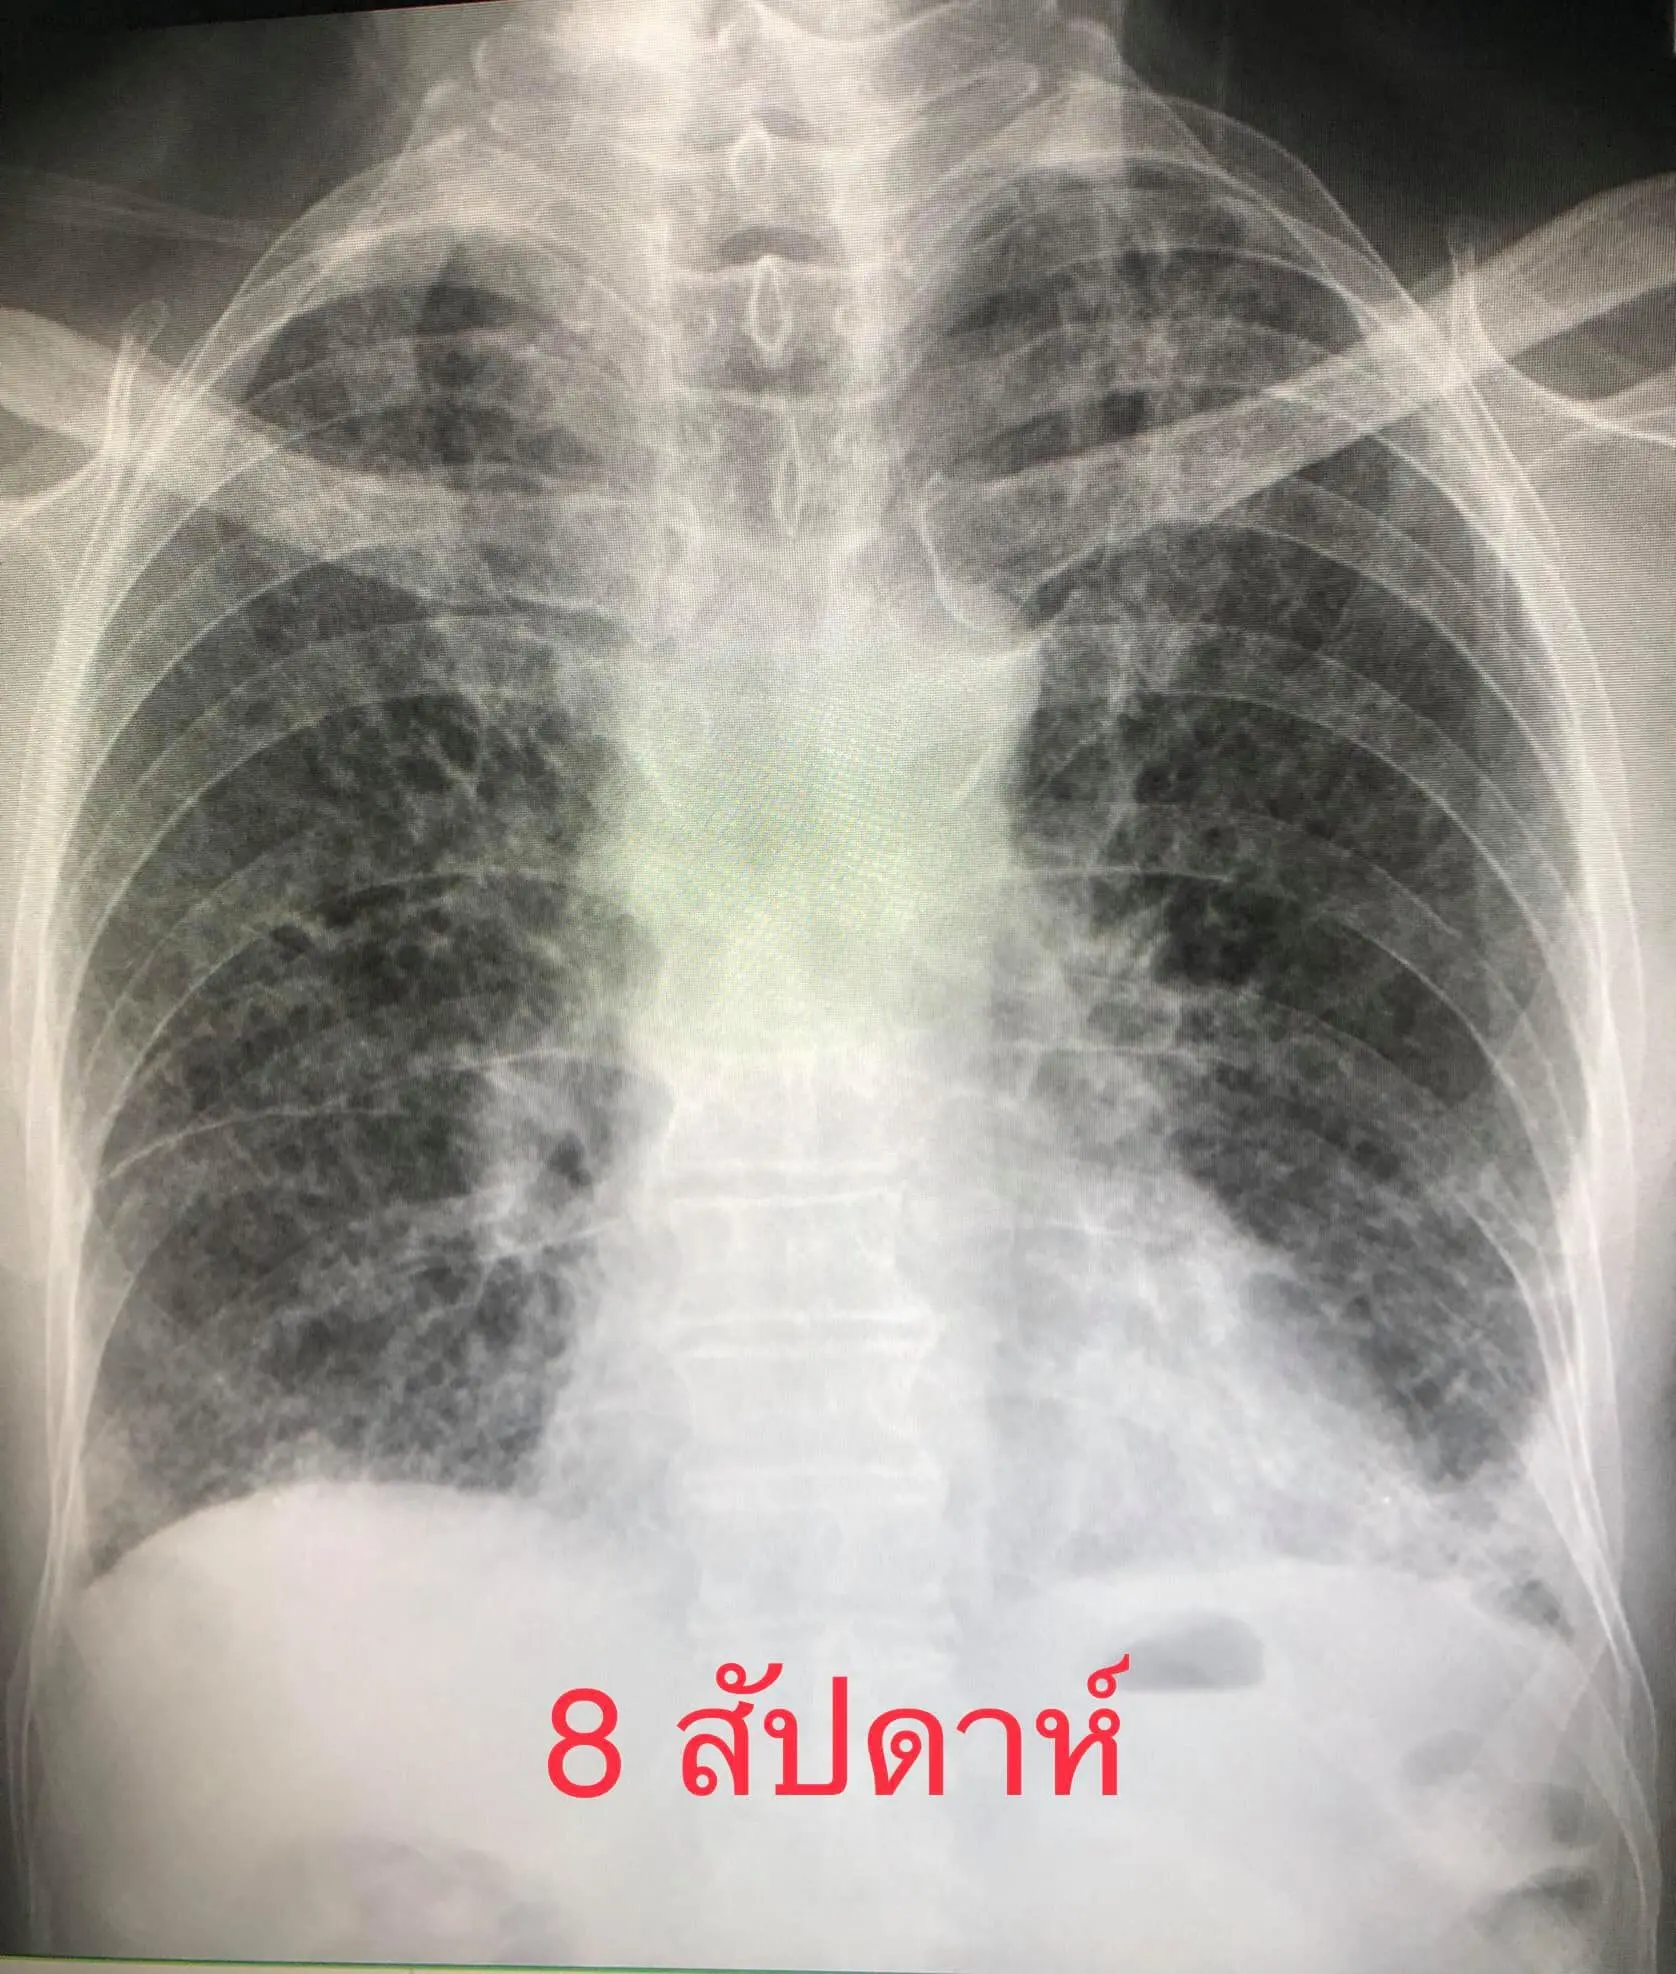

8 สัปดาห์หลังจากเริ่มป่วย มีไอเล็กน้อย ไม่มีไข้ เดินนิดเดียวก็เหนื่อย ยังต้องใช้ออกซิเจน 4 ลิตร/นาทีตลอดเวลา ระดับออกซิเจนในเลือดถึงจะขึ้นมาอยู่ที่ 95% แต่ถ้าไม่ใช้ออกซิเจน ระดับออกซิเจนในเลือดจะลดลงต่ำกว่า 80% เอกซเรย์ปอดยังผิดปกติ ลักษณะคล้ายพังผืด แต่ดีขึ้นช้าๆ (ดูรูป)